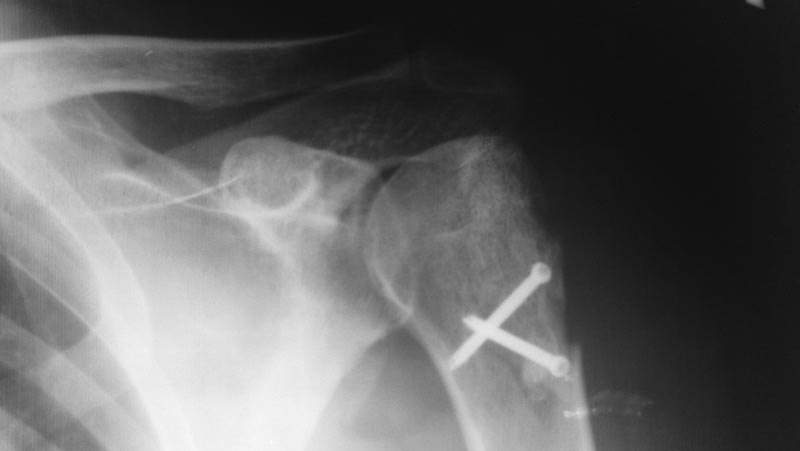

Пациент 45 лет, мужчина (парашютист). История болезни: травма вывих

плеча с оскольчатым

переломом большого бугорка левого плеча май 2013. Закрытое вправление

вывиха. Через 2

недели операция - открытая репозиция отломков с удалением костных

фрагментов остеосинтез

2-мя кортикальными винтами. При реабилитации выраженное ограничение функции,

консервативное лечение без эффекта. В ноябре 2013 в Киеве артроскопическая

субакромиальная декомпрессия. После операции сохраняется контрактура

плечевого

сустава. При осмотре рубец по дельтовидно-грудной борозде. Гипотрофия

дельтовидной.

надостной и подостной мышц. Движения ограничены: сгибание до 50,

отведение 45 (пассивные).

наружная ротация 5. внутренняя 10. Активные в основном за счет лопатки.

Дистальных

моторных, сенсорных и циркуляторных расстройств нет. На рентгенограммах

и СКТ дефект

задне-наружного части проксимального отдела плеча, выраженное сужение

субакромиального

пространства, дислокация плеча краниально. Вопросы: 1. Реверсивный

эндопротез? 2.

Открытый артролиз плечевого сустава, ревизия субакромиального

пространства, выделение

наружных ротаторов и их рефикс